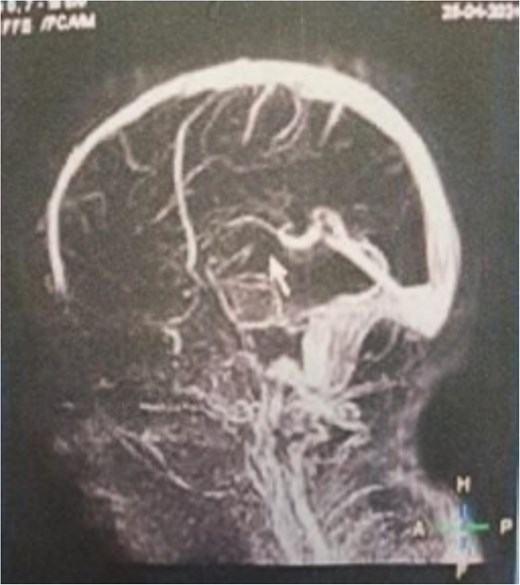

Additionally, magnetic resonance venography (MRV) confirmed a patent superior sagittal sinus with no encroachment of the lesion (Fig. 4). Differential diagnoses included dermoid cyst, eosinophilic granuloma, or benign fibro-osseous lesion. Surgical intervention involved en bloc excision under general anesthesia. A curvilinear incision was made over the mass, followed by subperiosteal dissection, which confirmed the lesion’s confinement to the diploë. Intraoperative frozen section analysis was not performed due to the lesion’s benign radiological features. Histopathological examination confirmed NOF, demonstrating ectodermal inclusion, cellular stroma of spindle-shaped fibroblasts arranged in a prominent storiform pattern, and scattered osteoclast-like giant cells. Notably, no evidence of mitotic figures, nuclear atypia, or necrosis was observed (Figs 5–7). The margins were free of lesional tissue. Postoperatively, the child resumed oral intake within 4 hours and was discharged on postoperative day 2 with analgesics. At the 6-month follow-up, the wound had healed without complications, with no recurrent lesion.

MRV sagittal view showing patent superior sagittal sinus with no encroachment of the lesion.